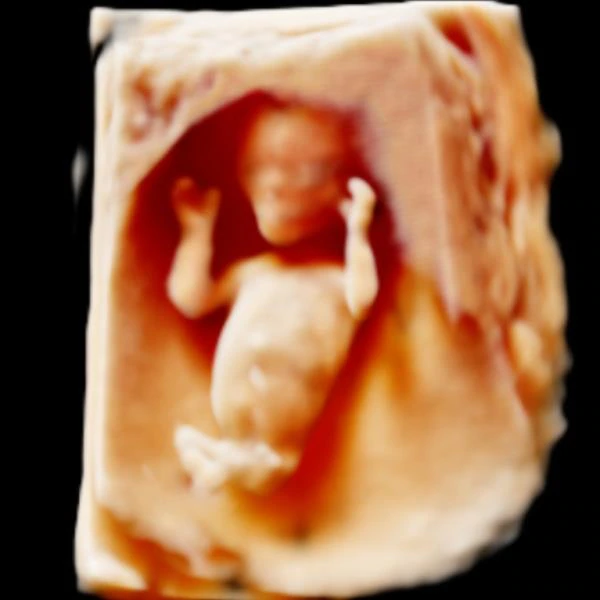

Fetal Anomaly Detection Scan

A mid-trimester level II or TIFFA scan performed between 20–22 weeks to examine the baby’s organs and detect structural abnormalities.